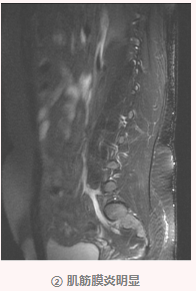

随后唐姐慕名来到我院骨伤科汪青春教授处就诊,确诊为腰椎间盘突出症、腰臀肌筋膜炎。

我院骨伤科学术带头人汪青春教授表示,腰椎间盘突出症和腰臀肌筋膜炎往往伴随出现,治疗需要兼顾,该病发病率较高,特别是长时间坐位工作的人群,手术治疗并非首选,大部分患者可以通过规范的保守治疗取得良好效果。

银质针属于我国古代“九针”疗法之一,它又吸取缇针、圆利针、长针和大针的特点制造而成,针的材质80%为白银,针身直径为1.1mm,约为普通不锈钢毫针的3倍。因其针身长、含银高具有良好的导热性。银质针刺入脊柱旁病变的肌肉筋膜组织,深达骨面,通过针体将热能导入深层病变的组织、关节,对周围嵌压的神经血管进行松解,消除肌腱附着点炎症,达到消除炎症、筋膜减压、组织修复的效果。